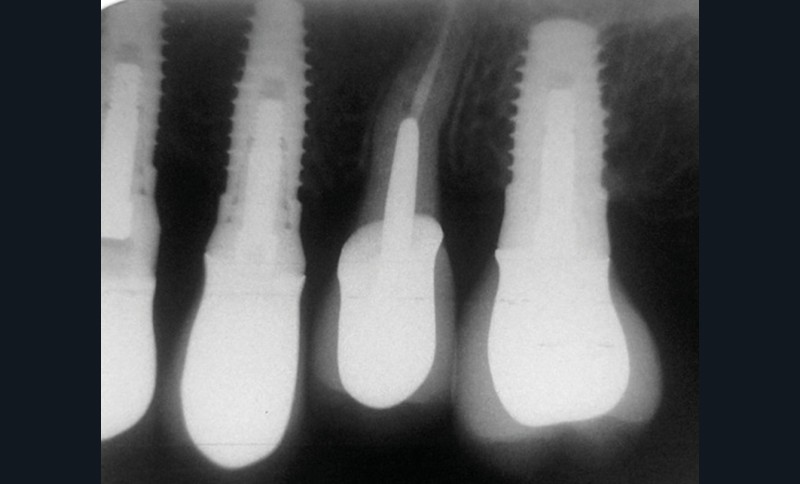

En mars 2016, la patiente se plaint d’une sensibilité sur la 25 et on note cliniquement une inflammation gingivale associée à un décalage apical du rebord marginal et de la ligne muco-gingivale en comparaison de leur situation visualisée au niveau des coiffes supra-implantaires. La couronne clinique est réduite et une infraposition avec une inocclusion d’environ 2 mm par rapport au plan d’occlusion et aux dents antagonistes est également notée (fig. 2 à 4). Un saignement au sondage ainsi qu’une poche de 5 mm en distal sont constatés. Le test de percussion est positif. Les tissus péri-implantaires adjacents ne présentent aucun signe de mucosite.

La radiographie péri-apicale au long cône confirme, sur la 25, un élargissement desmodontal, notamment en distal, des niveaux osseux mésio-distaux réduits par rapport aux clichés de contrôle précédents (les radiographies sont réalisées avec une technique parallèle avec des angulateurs de Rinn non personnalisés), un apex radiculaire normal et des niveaux osseux stables sur les implants adjacents (fig. 5). Le cisaillement systématique du fil dentaire lors de son passage confirme des points de contact très étroits entre 24, 25 et 26.

Le diagnostic d’ingression de la 25 pouvant être à l’origine d’un remodelage des tissus parodontaux et d’une récidive…